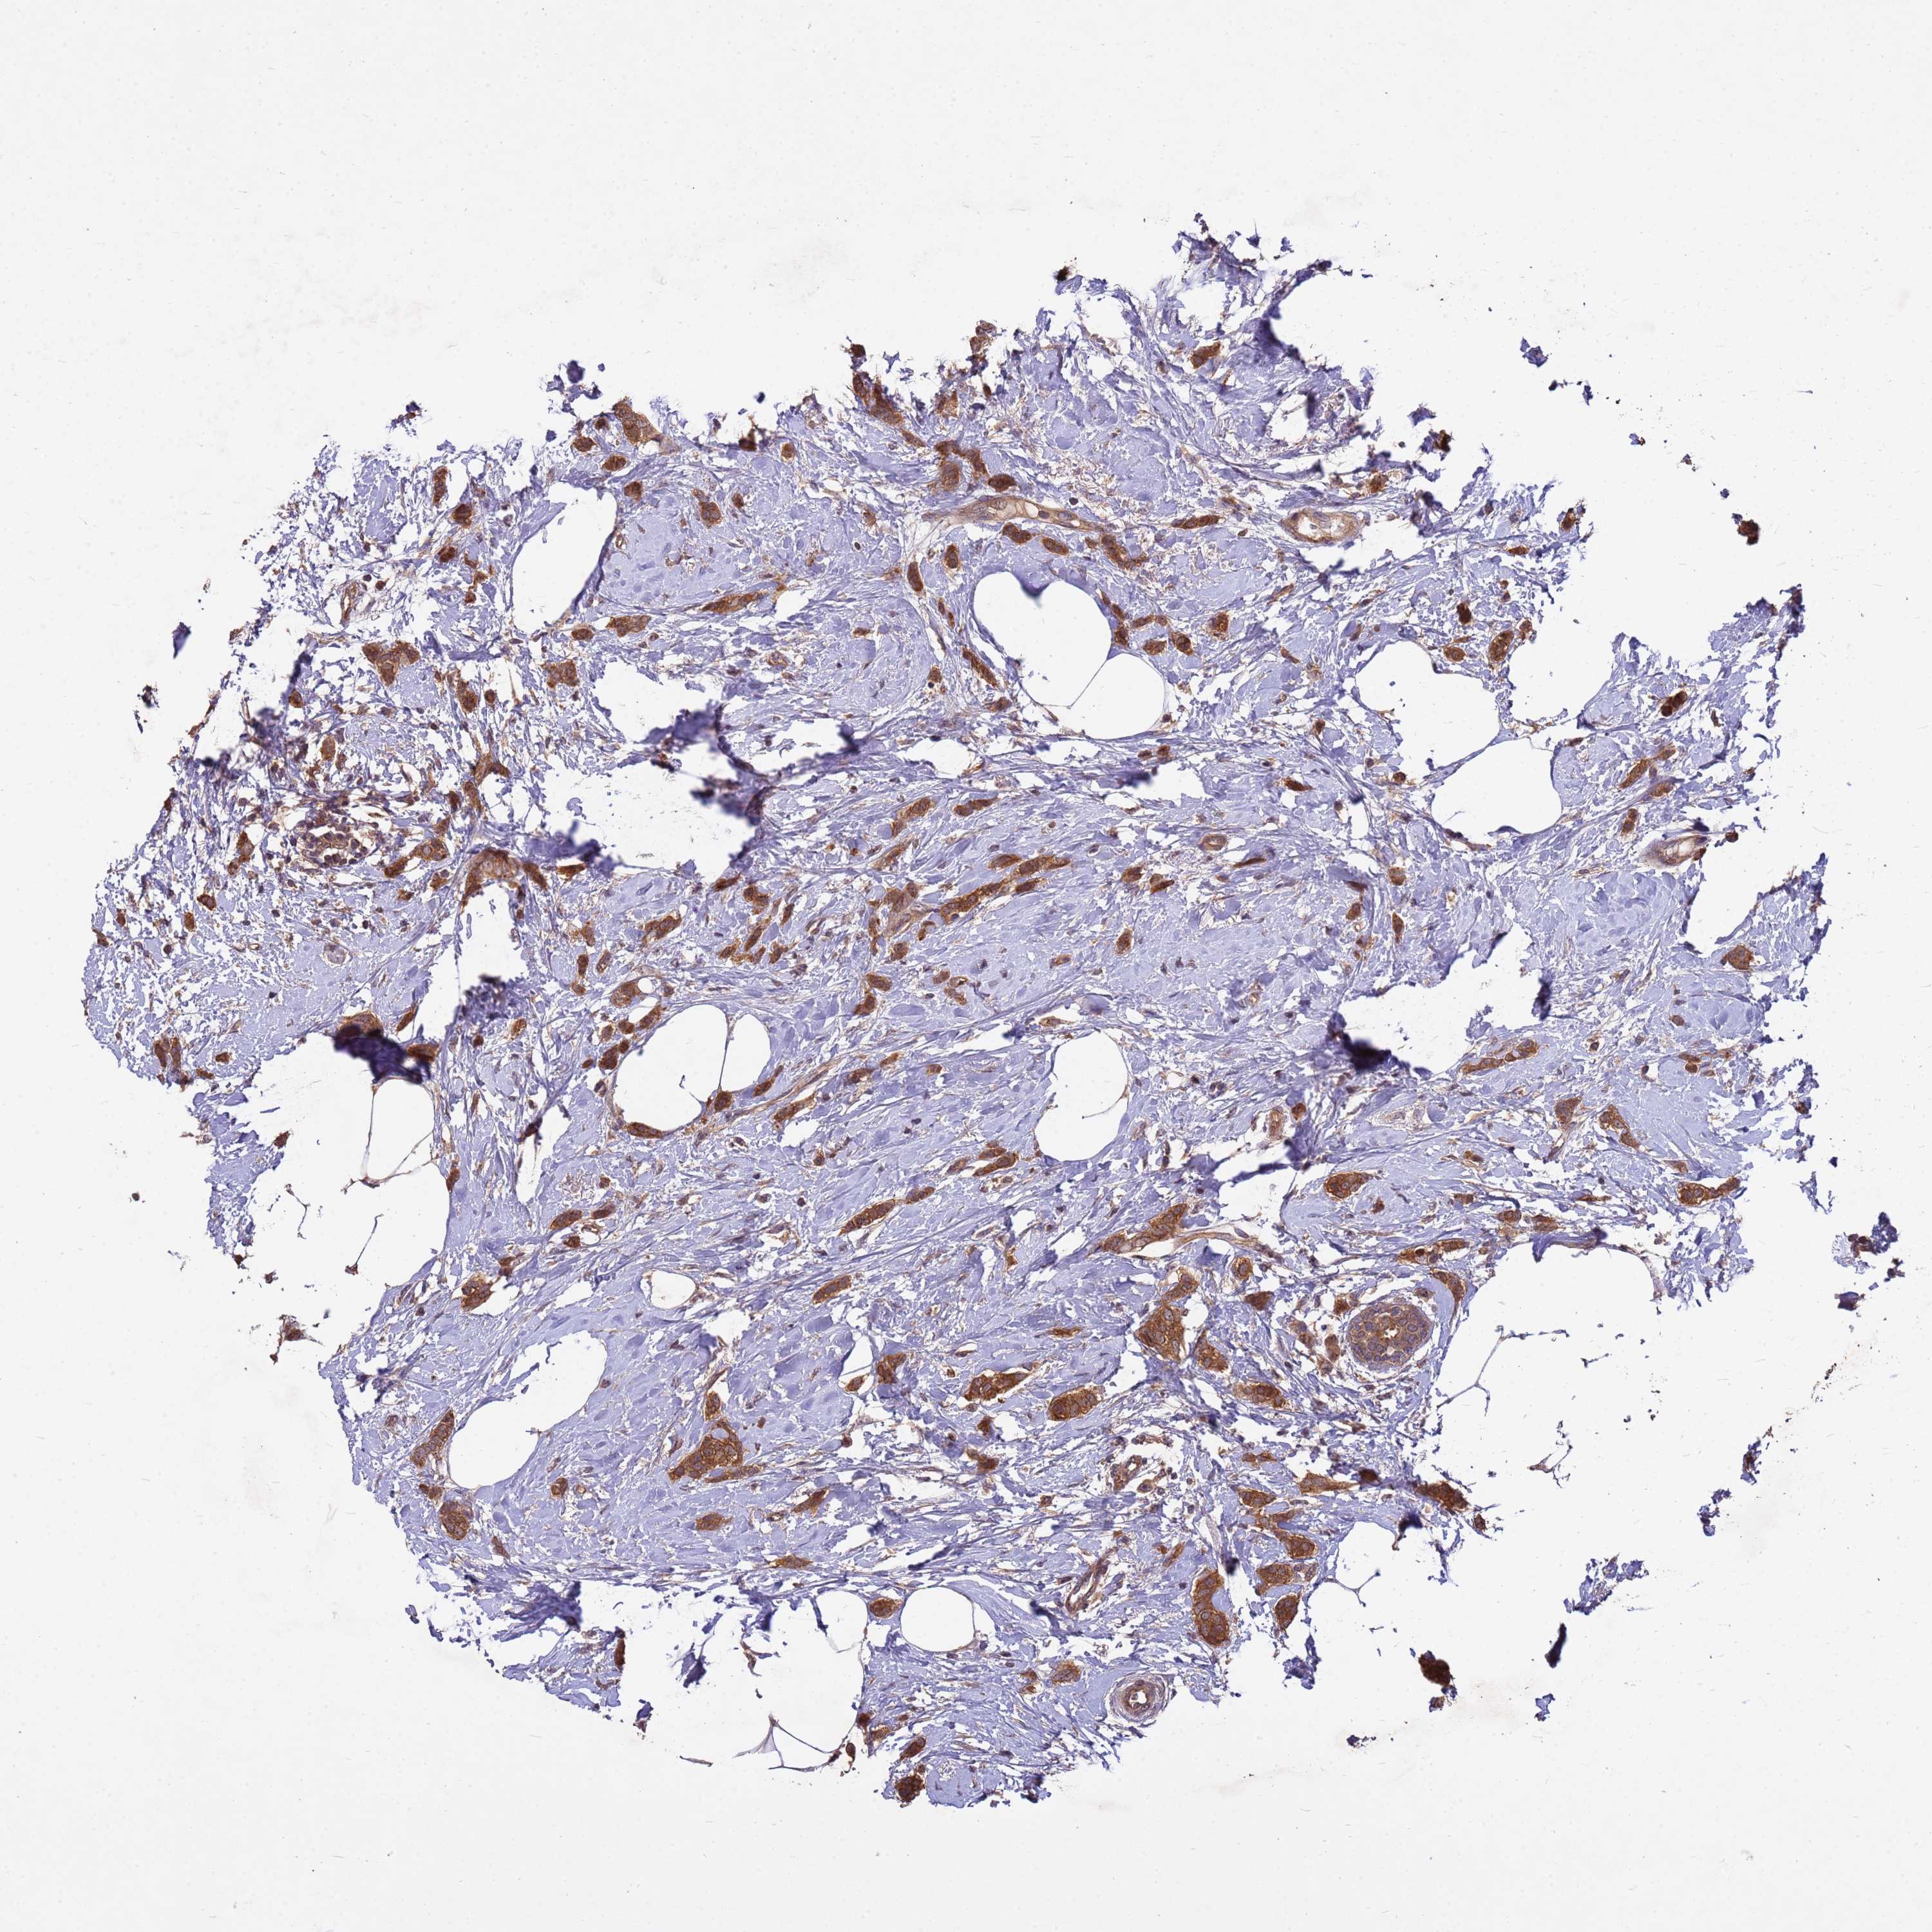

CANCER BREAST CANCER Show tissue menu

BRCA TCGA BRCA VALIDATION PROTEIN EXPRESSION

Breast cancer

Human cancer